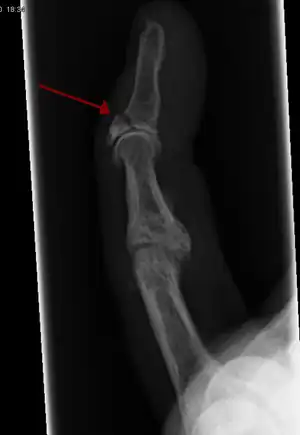

Avulsion fracture of the proximal middle phalanx on the palm side